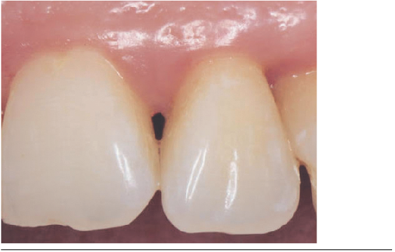

Se evaluó a los 60 días post-aplicación, observándose clínicamente aumento de volumen en sentido vertical y horizontal de las papilas (Figuras 3 y 4), mejorías en los parámetros estéticos y ausencia de signos clínicos de inflamación.

Se clasificaron los resultados en: triángulo negro cubierto totalmente y triángulo negro cubierto parcialmente. Además se graficó en una tabla la cantidad de milímetros ganados en cada papila. (Tabla 2).